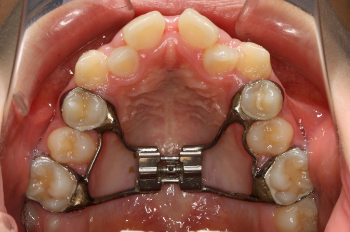

上顎急速拡大装置とは

上顎急速拡大装置は、上顎の幅を広げるための装置です。歯に固定し、中央のネジを少しずつ回すことで、上顎の骨を左右に拡大していきます。

上顎は左右に分かれた構造をしているため、成長期であれば骨の結合部分を広げることが可能です。